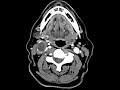

Tonsillar Squamous Cell Carcinoma

These images show asymmetric enlargement of the right palatine tonsil abutting the posterior aspect of the soft palate and right aspect of the uvula which may be secondarily involved by the mass. There are centrally necrotic right neck level IB and IIA enlarged lymph nodes compatible with metastasis as seen in HPV-related squamous cell carcinoma. The palatine tonsil is the most common subsite of oropharyngeal squamous cell carcinoma. 75% have adenopathy at presentation as seen in this case. HPV cancers are generally seen in younger patients and have a more favorable prognosis.